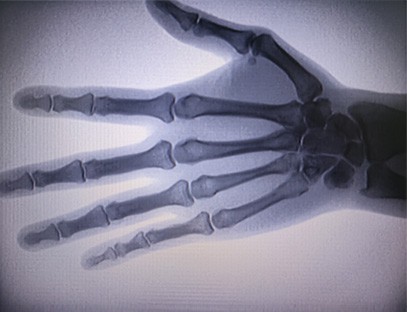

Prenosni rentgenski aparatje zelo varen prenosni instrument z nizko dozo sevanja, ki lahko pridobi visokokakovostne slike in hkrati zmanjša izpostavljenost sevanju. Kompenzira pomanjkljivosti velike bolnišnične opreme in ga je mogoče kadar koli premikati in prenašati. Posebej primerno za enote in posameznike z nezadostnim proračunom in nizkimi zahtevami po slikah. Naš rentgenski aparat nove generacije je opremljen z 10-palčnim velikim zaslonom visoke ločljivosti, ki ima večji razpon vidnega kota in lahko popolnoma vidi skozi celotno dlan, vključno z zlomi, izpahi, artritisom in kostnimi tumorji. Lahko se poveže s filmskim tiskalnikom za tiskanje ortopedskih filmov, lahko pa se uporablja tudi za industrijsko proizvodnjo in testiranje. Ni potrebe po temnici, neposredna perspektiva, opazovanje v realnem času. Ta stroj ima slikovni sistem visoke ločljivosti, ki lahko zelo jasno zajame slike katere koli strukture kosti. Zagotoviti najboljšo opremo za testiranje rentgenskih žarkov in rešitve za proizvajalce medicinskih, hišnih, industrijskih in elektronskih izdelkov, inšpekcijske in vzdrževalne oddelke ter raziskovalne laboratorije.

Specializacija:Zasnovan za potrebe ortopedskih klinik, posebej primeren zaRentgensko slikanjeokončin, kot so roke, zapestja, komolci, ramena, kolena, gležnji itd.

Jasna slika:Napredna tehnologija digitalnega slikanja se uporablja za zagotavljanje visokokakovostnih rentgenskih slik, kar zdravnikom pomaga pri natančni diagnozi bolezni.